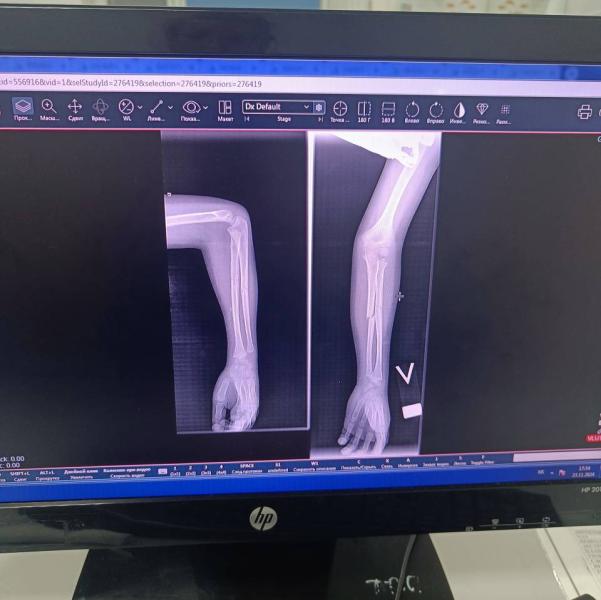

Сын повторно сломал руку...в июне упал с горки,носили гипс месяц,вроде не болело а вчера скакал и соскользнул с дина и упал на локоть,сломал в том же месте.Наложили гипс,но через неделю если на снимке не хорошо будет,то спицы...так как место не хорошее и обе кости.Переживаю теперь и за операцию и за школу((я же не обьясню темы так как учитель,или можно с гипсом в школу?а кто ему там будет помогать?рука левая,пис на всю ровную руку.